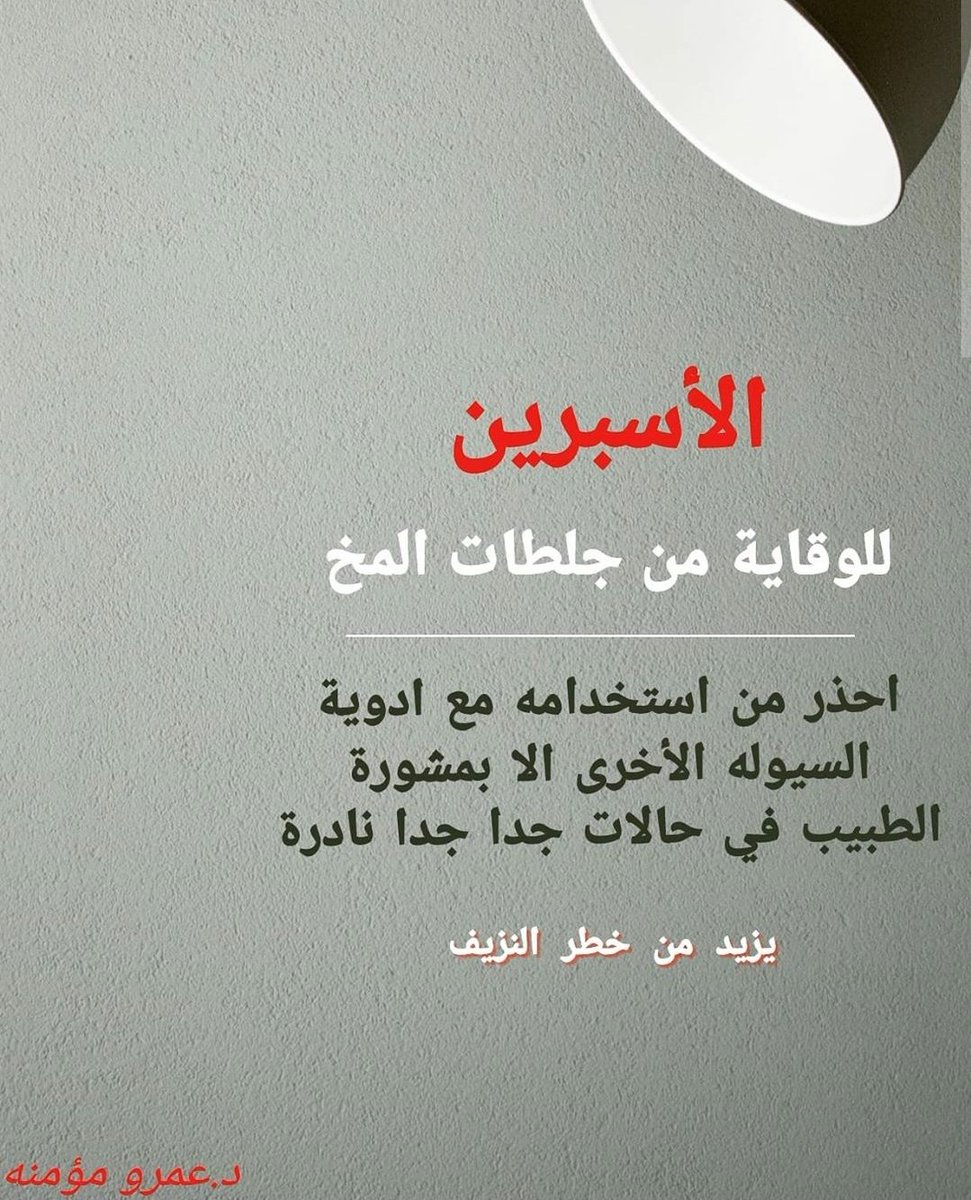

معلومات توعويه مفيدة عن #الاسبرين و #السكته_الدماغيه_الاقفاريه✌

💥بشكل عام

🧠الاصل علاج سيوله صحيح واحد يكفي إلا حالات نادرة قد نحتاج اكثر

♦️فلو استخدمت الاسبرين+البلافكس أو ادويه سيوله اخرى كالوارفارين تأكد من طبيبك المدة والسبب

💥بشكل عام

🧠الاصل علاج سيوله صحيح واحد يكفي إلا حالات نادرة قد نحتاج اكثر

♦️فلو استخدمت الاسبرين+البلافكس أو ادويه سيوله اخرى كالوارفارين تأكد من طبيبك المدة والسبب